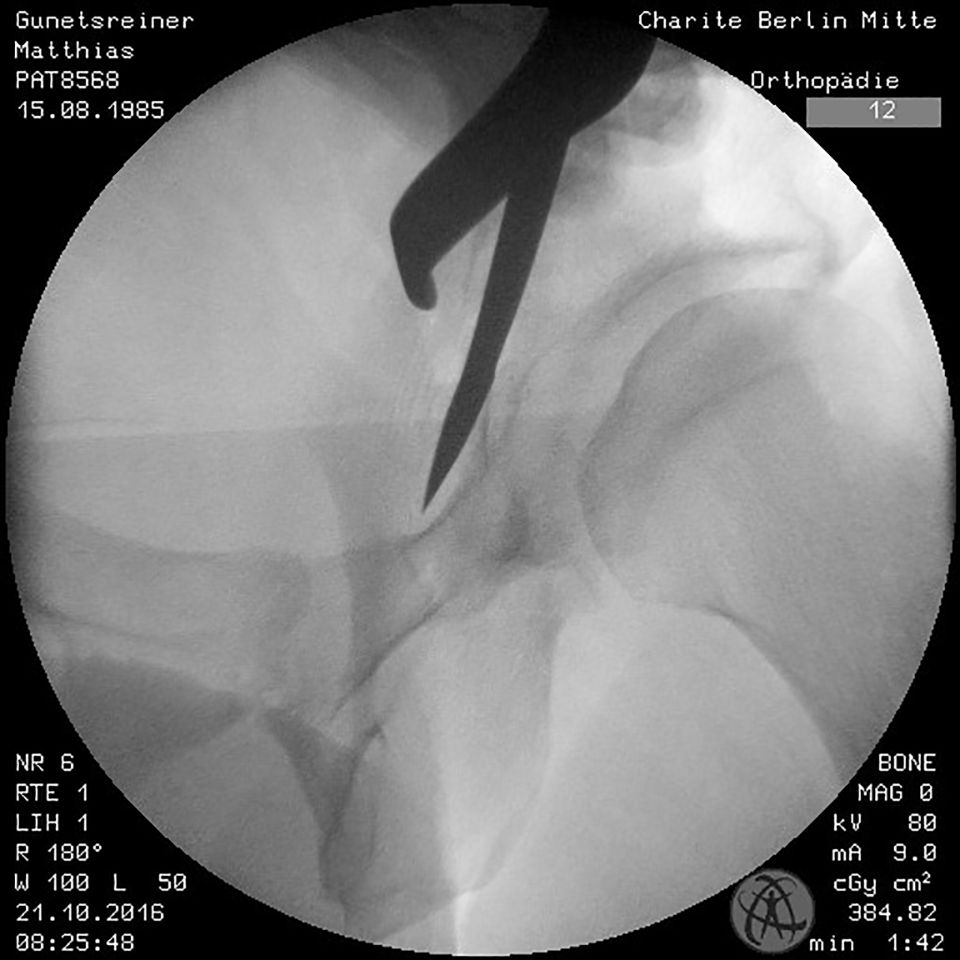

The incomplete ischium osteotomy, preserving the posterior half of the posterior acetabular column, is performed under radiological control with a curved 15mm osteotome. The osteotomy is initiated at the infracotyloid groove, which can be palpated very clearly with the tip of the osteotome, and ascends toward the spina ischadica (Fig. 7). At this point of the operation the surgeon needs to be aware of the anatomical proximity of the sciatic nerve, avoid Intraarticular penetration with the osteotome and guard against transection of the posterior column (Fig. 7, 8). To reduce the risk of nerve injury, the hip is flexed and abducted for the osteotomy of the medial ischium (Fig. 9). For the osteotomy of the lateral ischium the leg is extended and externally rotated.

The next step is to strictly move on the hip joint capsule, which was displayed before, between the iliospoas and rectus muscles with a Cobb-raspatory towards the os ischium. This interval is used to insert a curved osteotom for the osteotomy of the os ischium.